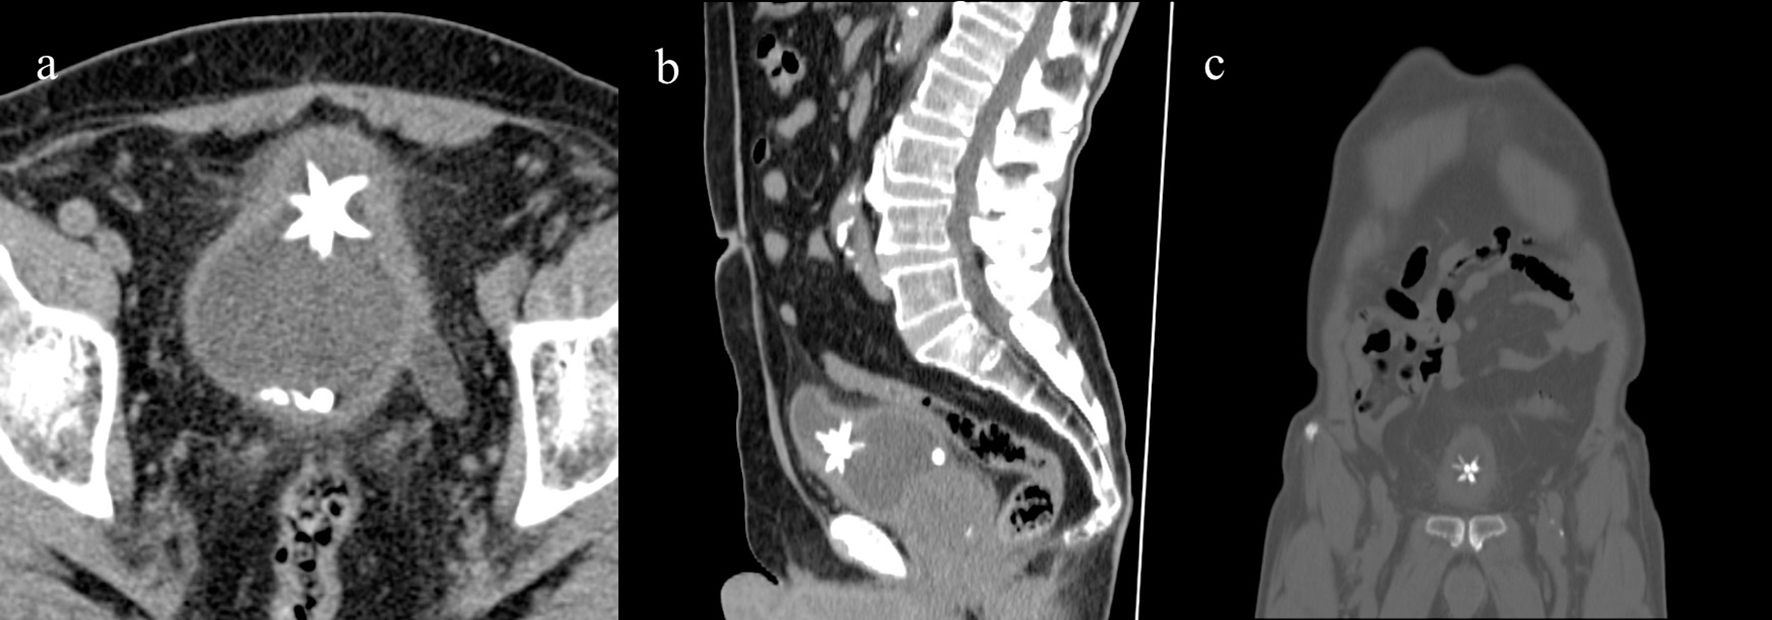

A 84-year-old man with cognitive impairment and non-specific abdominal pain came to our observation. Relatives stated that the man had suffered from benign prostatic hypertrophy for many years and that there was also a history of chronic renal failure and diverticulosis. A month earlier the patient had an episode of macroscopic hematuria. Hematological, microbiological and biochemistry examinations revealed no abnormalities, but confirmed only high creatinine levels. An abdominal computed tomography examination (CT) without contrast was also requested to rule out diverticulitis. The study was performed on a Philips Brilliance CT 16-slice scanner and was completed by multiplanar (MPR) (Fig. 1), 3D maximum intensity projection (MIP) and volume rendering (VR) reconstructions (Fig. 2). A stone of 3 × 2.4 × 3.2 cm with a central dense core and peripheral and speculated projections was visible in the poorly distended bladder. The appearance of the stone was compatible with a Jackstone calculus (Fig. 3). It was located between the bladder body and the dome (Fig. 1a, b). At this point, the bladder walls were also thickened (Fig. 1a). Other little stones with regular appearances were also visible at the part of the bladder base. The patient’s prostate was enlarged, measuring 5.7 × 5 × 5.3 cm (Fig. 1b).

![]() Click for large image | Figure 1. Axial CT showing the Jackstone calculus between the bladder dome and the body with adjacent wall thickness. Other calculi with regular appearances were also visible at the bladder base (a), MPR reconstruction on sagittal (b) and coronal plane (c). |